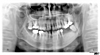

Les cas extrêmes de déchaussement peuvent être réhabilités grâce à des couronnes ou des bridges fixes supportés par des implants et reconstruisant toutes vos dents.

cas traité18

Prothèse complète